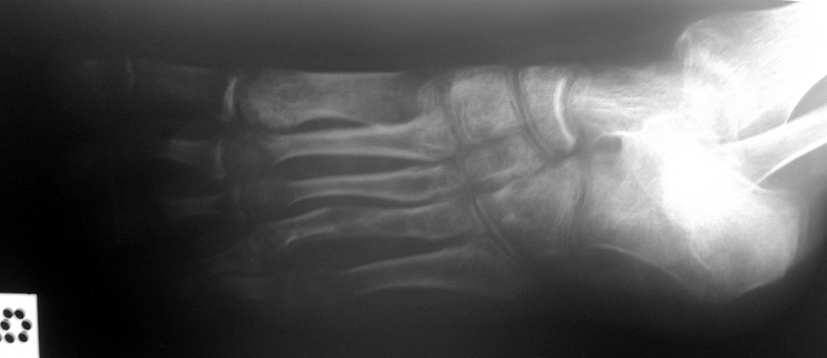

El parmağı (metakarp) ve ayak parmağı (metatars) kısalıkları doğuştan tek başına, geniş bir sendrom grubuyla birlikte, travma sonrası, Freiberg hastalığı (avasküler nekroz) sonrası görülebilir.

Metakarp kısalığında kozmetik görünümün bozulması ve dominant elin kullanımı sırasında yorulma, metatars kısalığında ise kozmetik haricinde metatarsalji, kısa parmağın dorsale kayması sonucu deformite oluşması, plantar yönde açılanması sonucu ağrı ve bası ülserleri, ve ayakkabı giymede zorluk nedeniyle ameliyat gerekebilir.